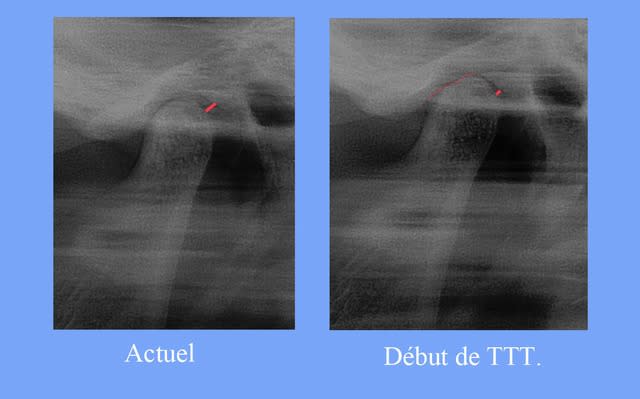

"""Quand aux radios, on ne voit effectivement aucune différence entre avant et après"""

Voici les différences objectivées en rouge, j’espère que certains verront mieux

la tête du condyle n'appuie plus en post.

Puisque tu m’as l’air de faire des progrès dans la lecture des Rx.

regarde l’évolution, le changement d’opacité du centre de la tète du condyle

(les Rx ont été prises avec le m appareil, et les m réglages)